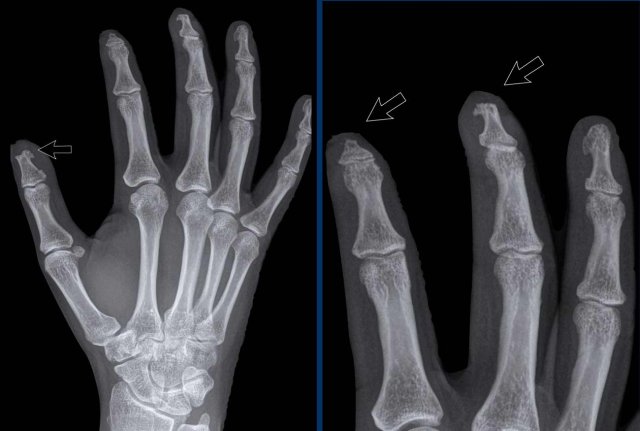

Progressive psoriatic arthritis

1. The picture on the left shows marginal erosions (black arrow) and subtle bone formation (blue arrow) of the IP joint.

2. Later on, it progresses to the typical pencil-in-cup deformation.

The distribution and the bone formation makes the diagnosis of rheumatoid arthritis unlikely.

The marginal erosions and the absence of DIP involvement in other joints makes the diagnosis of erosive osteoarthritis unlikely, although pencil-in-cup can look like the gullwing deformity in erosive osteoarthritis.